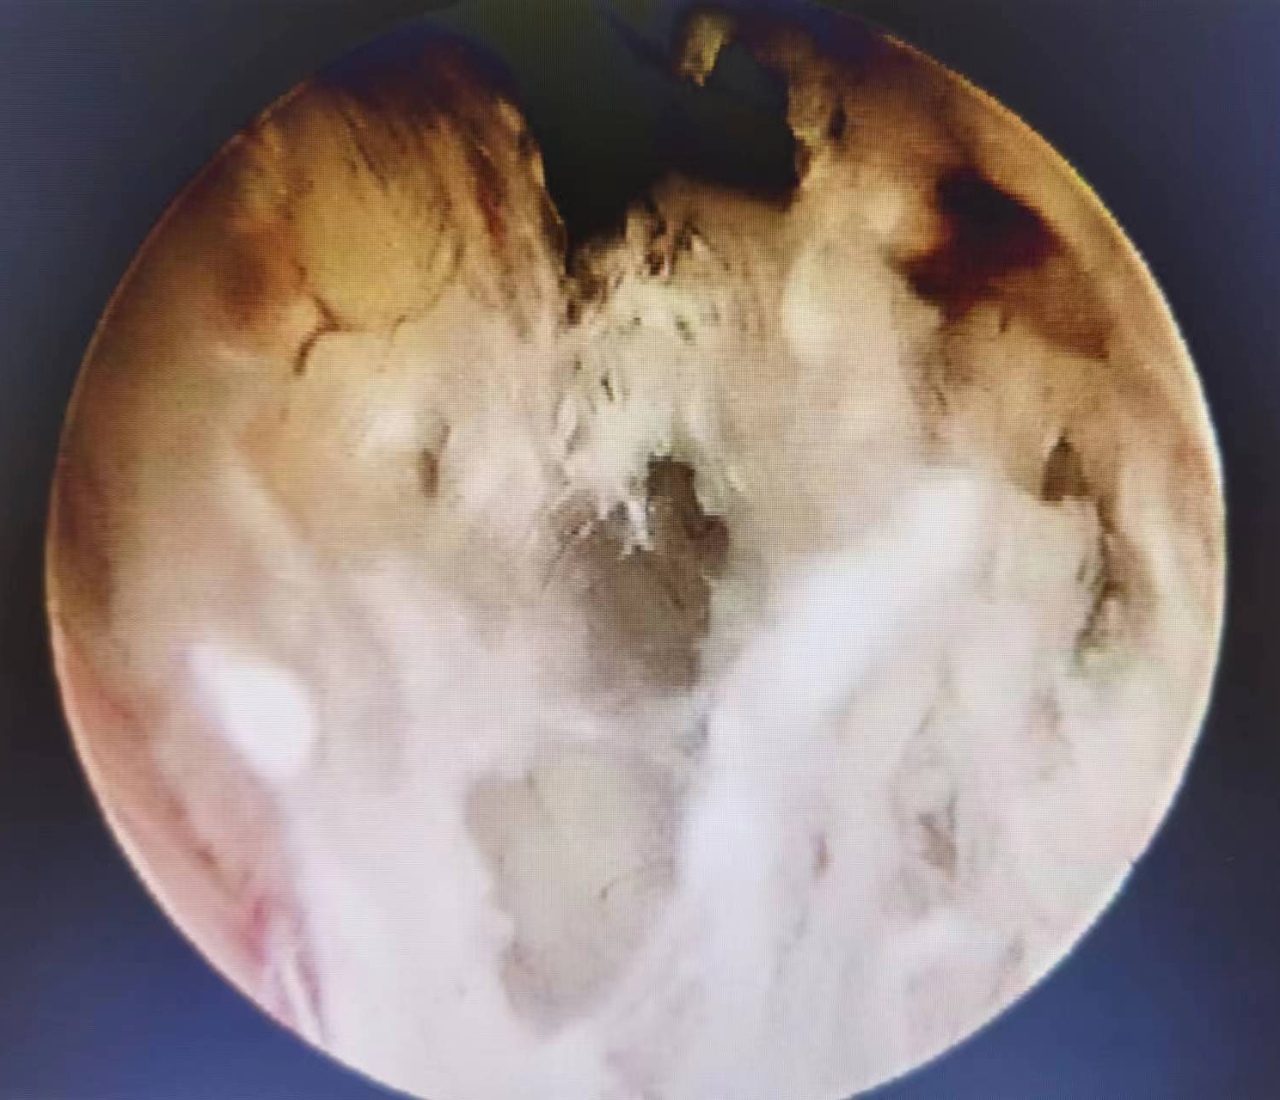

宫腔镜下可见子宫内膜息肉样增生

血管明显扩张扭曲

内膜增厚伴增生小血管

术后病理回报,为子宫内膜样腺癌。由于发现及时,李女士得到了及时治疗。